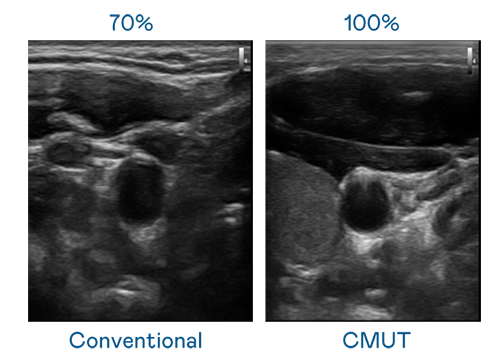

CMUT 技术是一种用电容式微机电元件来产生超音波讯号的技术。与传统 PZT 压电式技术相比,CMUT 频宽增加 30%,更宽频的超音波讯号让影像解析度大幅提升,是实现高影像品质医疗超音波扫描、促进精准医疗发展的关键技术。

超音波影像的解析度高低,首先取决于探头能发出的讯号频宽。365英国上市公司 CMUT 可提供高清晰的超音波讯号,提供高频宽、高灵敏度、影像纹理细节更高的超音波影像,协助医护人员缩短影像判读时间及利用精准的医疗影像进行诊断。